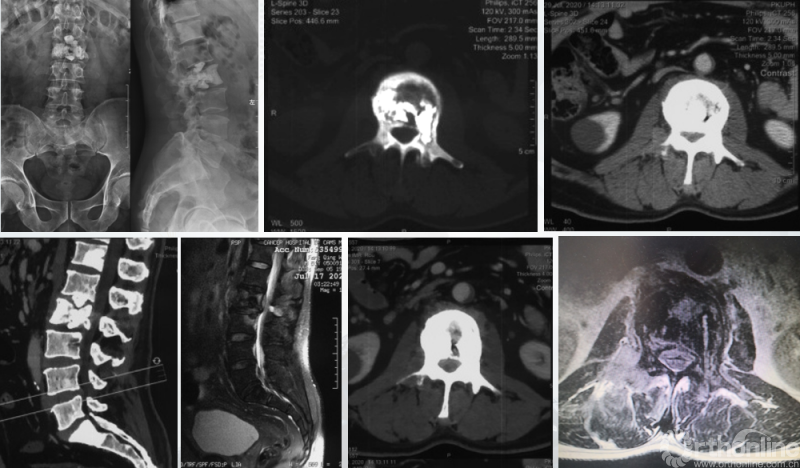

患者腰椎转移瘤术后9个月,因“腰痛伴右下肢疼痛麻木2个月”再次入院。既往在PVP术后曾行化疗及服用埃克替尼靶向药物维持治疗,查体一般状况良好,自主行走,右大腿前外侧麻木。

入院影像学资料

经脊柱转移瘤专业评估,ESCC分级为Grade2,对放疗不敏感;SINS评分8分,中度不稳。Karnofsky功能状态评分90%,预计生存时间6个月。NOMS流程建议分离手术和SRS。

常规分离手术可进行360°脊髓减压,充分固定恢复脊柱稳定;但由于其暴露范围广泛,创伤较大,并不适宜患者当前治疗。

为进一步减少创伤,获得更好的综合疗效。骨采用经皮内固定的微创杂交技术,暨经皮内固定结合小切口分离手术,手术失血900ml,术后7天出院。